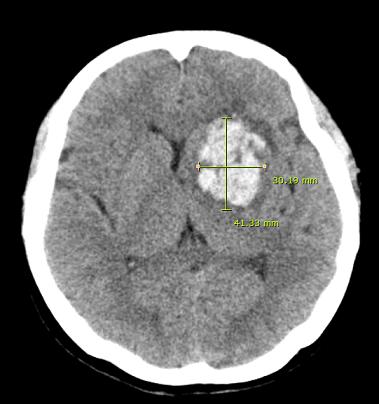

- 진단 및 평가: CT 또는 MRI 스캔을 통해 출혈의 위치, 정도 및 환자의 전반적인 상태를 파악합니다.